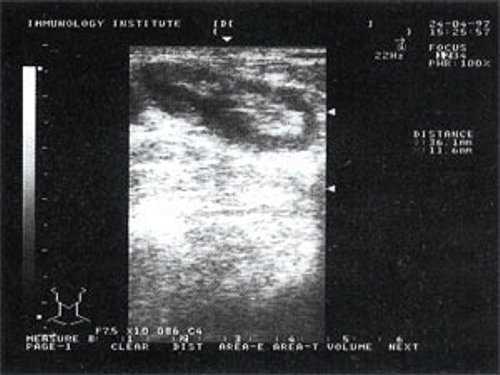

Рис. 2. Эхографическое изображение непальпируемого югулярного лимфатического узла на фоне остаточных явлений после перенесенного фарингита.

Мы установили, что, как правило, более округлая конфигурация лимфатического узла при его размерах, превышавших 10 мм, сопровождалась небольшими болевыми ощущениями, и более выраженной простудной (воспалительного характера) симптоматикой. Лимфатические узлы менее 10 мм чаще всего плохо пальпировались, либо вообще не выявлялись пальпаторно. Во всех случаях эхографически хорошо дифференцировался гипоэхогенный кортикальный слой и широкое, средней или чуть ниже средней эхогенности изображение области ворот лимфатических узлов. Четкость дифференциации составных частей лимфатического узла была снижена при размерах менее 5 мм. Мы отмечали различную толщину гипоэхогенного изображения области коры лимфатического узла: от очень широкой - при выраженности или прогрессировании воспалительного процесса, до узкой - на фоне положительной динамики.